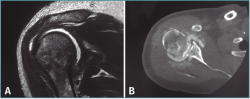

Ante esta situación, se solicita una tomografía computarizada (TC) para comprobar las lesiones asociadas. En esta se muestra una persistencia de la luxación posterior, asociada a una lesión de Hill-Sachs y de Bankart invertidas (Figura 2).

Figura 2. Cortes coronal (A) y axial (B) de la tomografía computarizada en los que se observan las lesiones de Hill-Sachs y Bankart invertidas.

El postoperatorio transcurre sin incidencias, comprobándose la correcta congruencia articular en la resonancia magnética (RM) a las 4 semanas de la cirugía y en la artro-TC de control a los 2 meses de la misma (Figura 3). Tras la cirugía se mantiene inmovilización con cabestrillo durante 4 semanas, iniciándose el tratamiento físico rehabilitador mediante ejercicios pasivos y asistidos a la tercera semana, ejercicios activos a las 6 semanas y fortalecimiento muscular a los 3 meses.

Figura 3. Corte coronal de resonancia magnética (A) y corte axial de artrotomografía computarizada (B) postoperatorios en los que se observa la reducción de la cabeza humeral en la glena sin otras lesiones asociadas.